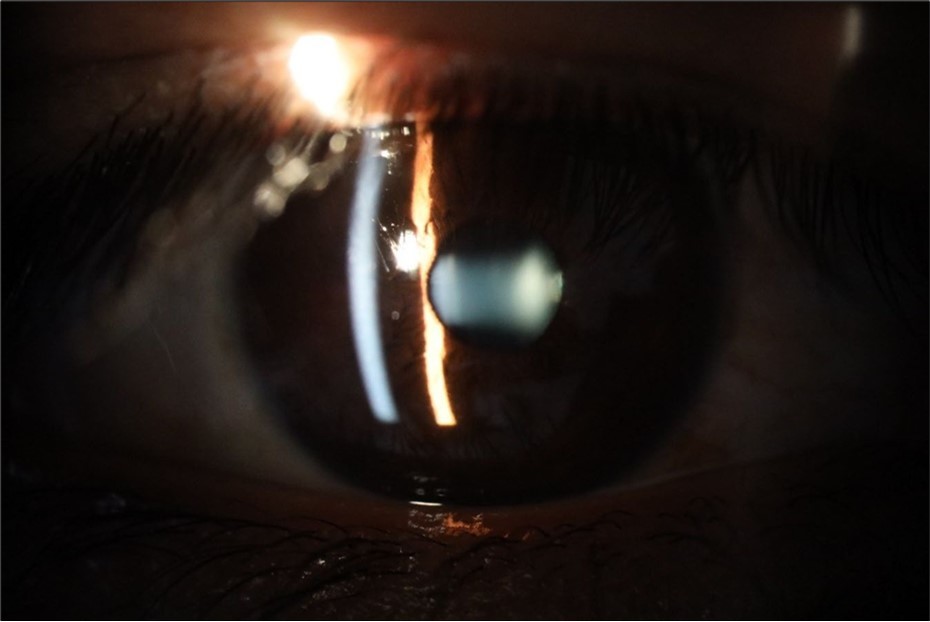

Figure 15.The photograph shows better specular reflection, compared to the first day of the exam.

Figure 16.The anterior segment of the right eye shows the vitreous with greater transparency. The cornea and lens, as well as the anterior chamber, are in good condition.